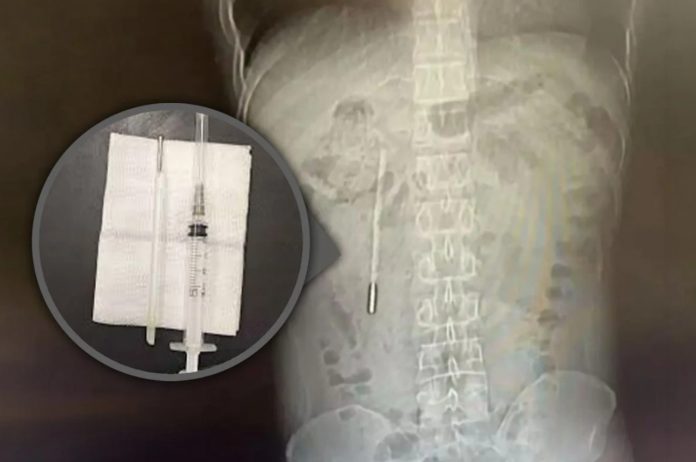

Un bărbat din China în vârstă de 32 de ani a ajuns la spital acuzând dureri abdominale, însă investigațiile au scos la iveală un caz medical rar: un termometru cu mercur înghițit în copilărie, care a rămas în corpul său timp de două decenii.